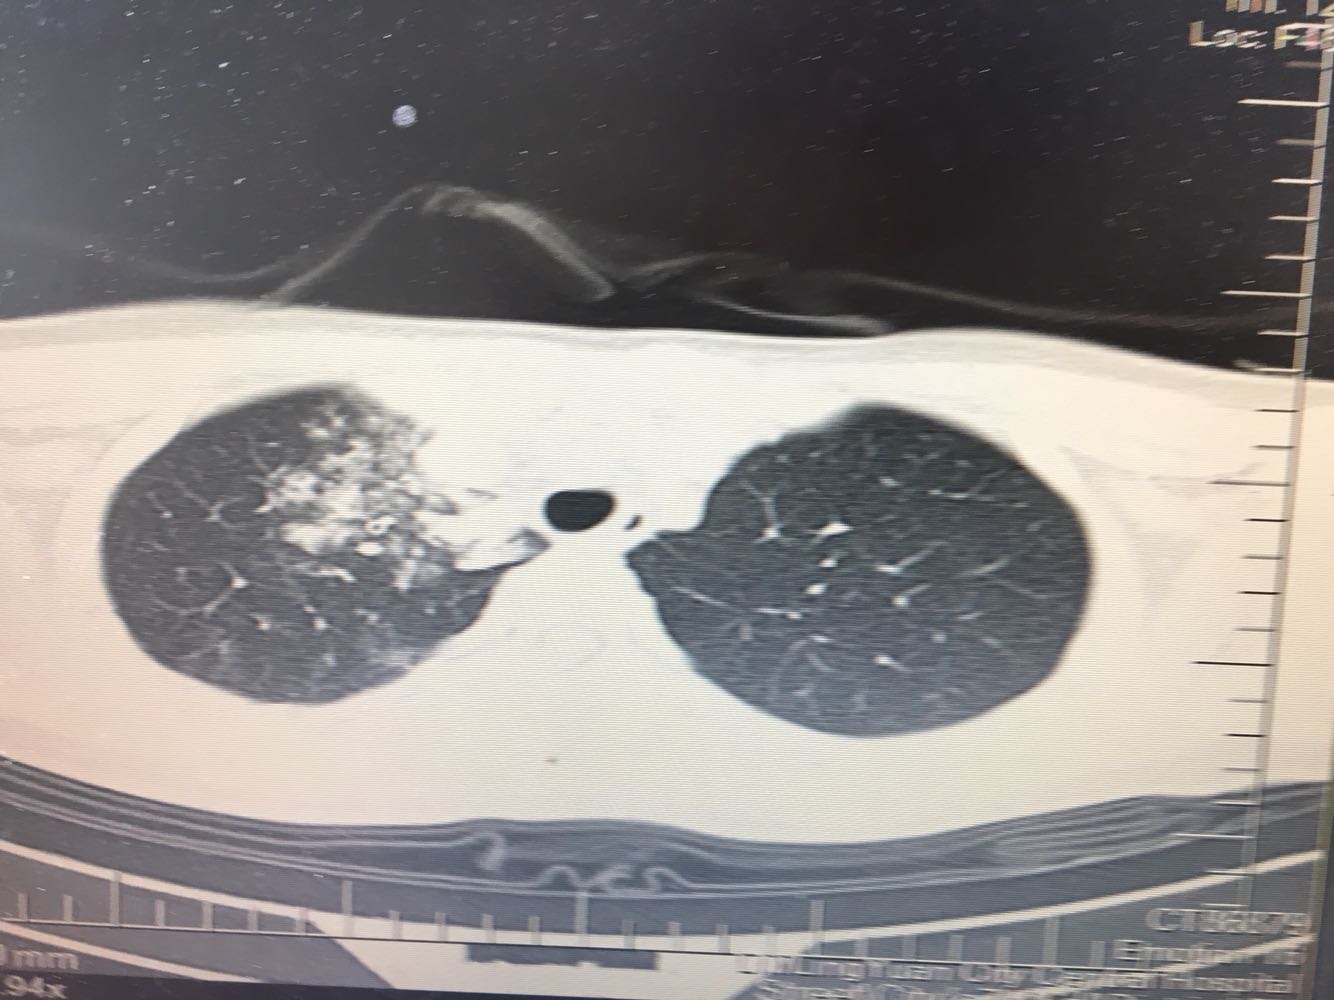

女,26岁,咳嗽1周,咳痰不畅,咽喉痒,口服阿莫西林无好转,昨日发热,体温38.5摄氏度,于门诊查肺CT后以肺炎收入院,病来无盗汗,无咳血,无消瘦及乏力,无头痛,无肢体酸痛,饮食睡眠可,二便正常

神清言明,咽部无充血,扁桃体不大,双肺呼吸音清,无罗音,服软无压痛。

支原体肺炎?肺结核?

支原体抗体1:160,结核抗体弱阳性。支原体肺炎个别可见上叶病变,该患无结核中毒症状,考虑支原体肺炎可能性大,但肺尖为结核好发部位,需要抗炎治疗后复查观察疗效。